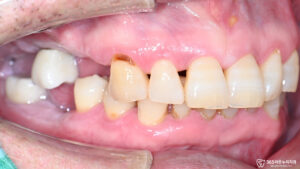

식사 중 딱딱한 무언가를 씹는 순간 갑자기 어금니가 흔들리면서 심한 통증을 느끼신 환자분께서 발치를 원한다며 급하게 오산역 치과 로 내원하셨습니다.

환자분은 갑작스러운 상황에 많이 당황하신 상태였고, 통증으로 인해 음식을 제대로 씹기조차 어려워하셨습니다.

정밀한 검진과 촬영을 통해 진단한 결과,

왼쪽 아래 작은 어금니에 심각한 치주염(검게 보임)이 진행되어 치아를 보존하기 어려운 상태였습니다.

치주염으로 인해 치아 주변의 잇몸뼈가 많이 손상되었고, 치아의 뿌리까지 흔들리는 상황이어서 즉시 발치를 진행할 수밖에 없었습니다.

더 큰 문제는 환자분께서 오른쪽 치아들이 이미 없는 상태로 오랫동안 지내오셨다는 점이었습니다.

한쪽으로만 음식을 씹어야 하는 상황에서 남은 치아마저 손상되자, 일상생활에서 식사가 큰 고통이 되어버린 것입니다.